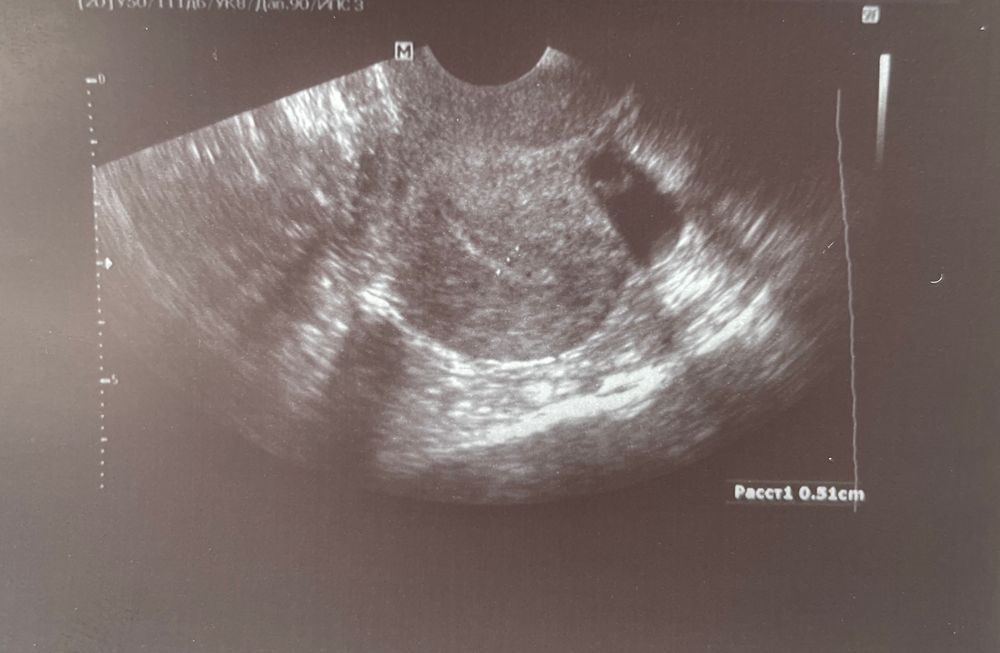

Образование в матке

Кто разбирается, что это за образование? Полип? Должен был быть протокол в мае

По снимку сложно точно определить тип образования. Возможные варианты могут включать кисту, полип или другие доброкачественные новообразования.

Полипы обычно описывают в структуре эндометрия. У вас по описанию скорее похоже на миому или очаг аденомиоза. А врач что ли никак не прокомментировал свои догадки?

Может миома? Или полип? Если есть возможность пройти УЗИ у другого врача, пройдите. Образование не большое, но я думаю это все таки полип, если это он, то только хирургически удалять его!